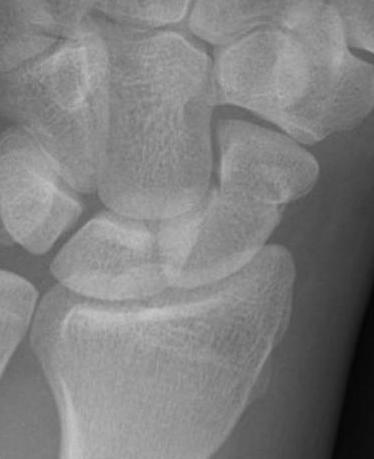

X-ray

5 images

- PA / lateral

- PA in 45° oblique pronation / PA 45o oblique supination

- PA in ulna deviation

Scaphoid waist fracture 1 mm displaced

Scaphoid fracture with significant displacement

Scaphoid proximal pole fracture